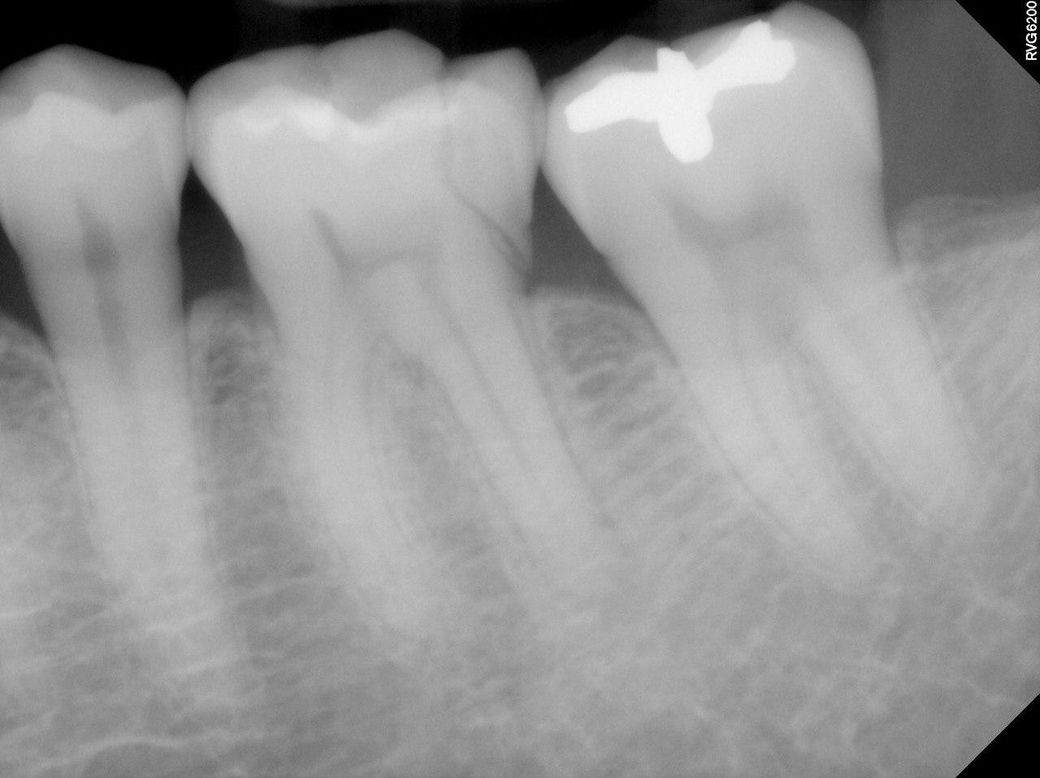

어금니 파절을 치료하기 위한 병원 선택

7월26일 어금니가 파절(왼쪽 아래 2번째 어금니의 1/5이 아래방향 사선으로 깨짐)되어서 움직이는 상태 입니다.

치료는 깨진 부분을 제거하고 레진으로 채우고 크라운으로 쒸우는 치료를 받아야 한다고 합니다.

깨진 부분이 신경과 가까워서 신경 헤드부분만 제거하고 같은 방법으로 치료한다고 하셨습니다.

추가로 잇몸아래까지 깨진부분을 레진으로 채운경우

치조골이 녹아서 결국 빠지게 될 수도 있나요?

+말씀하신 것처럼 파절 라인이 치은 하방, 치조골 라인이라 그냥 레진으로는 방습도 안되고 못하고요. 치은절제술이나 치관확장술, DME(deep margin elevation)시술 필요할 것 같습니다.

일단은 치아 깨진부분이 넓어서 크라운 치료를 하셔야될것같고 신경치료 가능성도 있어 보입니다.